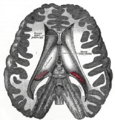

Pineal gland or epiphysis (in red)  | |

The pineal body is labeled in these images.